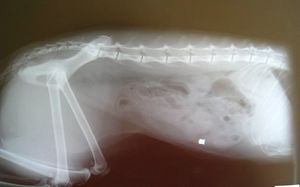

Anna is a beautiful looking, petite cat who is just over two years old. About a year ago, when she was homeless, this quiet girl was shot in the abdomen with an air rifle bullet which punctured her intestine in seven places, causing internal bleeding. (The photos at the bottom show the entry point and the bullet is clearly visible in her x-ray). Fortunately, the bullet was able to be surgically removed and the intestine expertly repaired. Anna has recovered well, but understandably, she is timid with strangers and prefers to spend most of her time indoors. She is easily bullied by other cats and is afraid of dogs and noisy young children, so she needs an extra-special home.